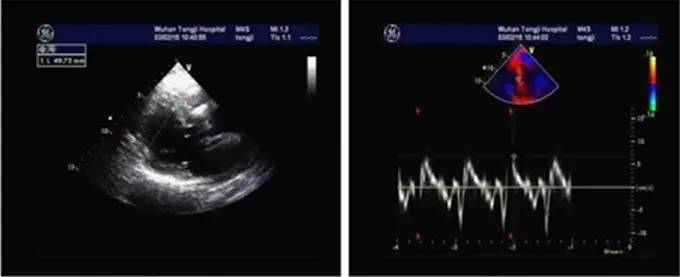

患者入院后完善超声心动图检查(图2),结果显示心脏形态正常,结构无明显变化,仅存在左室节段性室壁运动异常[二尖瓣口左房侧以及三尖瓣口右房侧收缩期可见轻度反流血流信号及湍流频谱;二尖瓣口舒张期血流频谱测值:E峰96 cm/s,A峰58 cm/s;左室射血分数(LVEF)66%;室间隔二尖瓣环处E' 10 cm/s,A' 10 cm/s,S 7 cm/s]。但值得注意的是,虽然看似心功能尚可,但与患者症状不符,而其关键点就在于该患者存在射血分数保留的心力衰竭(HFpEF)。

图2. 超声心动图检查